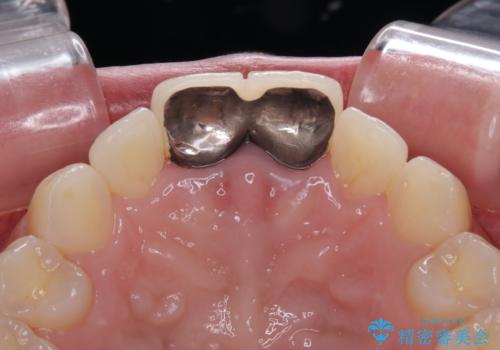

- 保険診療で装着した前歯の色調と厚みを気にして来院された患者様です。

レントゲン写真より、右側の前歯は神経が失活している可能性があり、クラウン除去後に診察を行ったところ、やはり失活していました。

根管治療を行った後に、両歯ともに土台を植立し、オールセラミッククラウンにて補綴治療を行うこととしました。